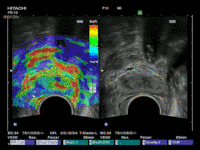

Die Echtzeit-Elastographie ist eine Messung der Elastizität des Prostatagewebes. Dies ist ein bildgebendes Verfahren, mit dem tumorverdächtiges Gewebe in der Prostata mittels verschiedenen Farben auf dem Ultraschallmonitor angezeigt wird. Dabei misst die Ultraschall-Elastographie die Elastizität des Gewebes, also die Härte des Prostatagewebes indem es die Reaktion des Gewebes auf Druck misst. Tumorgewebe ist in der Regel härter als gesundes Gewebe. Die harten tumorverdächtigen Areale werden so aufgespürt und können sofort gezielt biopsiert werden. Die Ultraschall-Elastographie erzielt beim Aufspüren von Tumorbereichen in der Prostata deutlich aussagekräftigere Ergebnisse als der herkömmliche Ultraschall.

Zunächst einmal werden die bereits durchgeführten und von Ihnen mitgebrachten MRT-Bilder (1,5T-3T, mit/ohne rektale Spule, DICOM-Format) in unser Gerät eingelesen. Anschließend werden die suspekten Areale und die Organgrenzen der Prostata in der MRT-Bildgebung markiert. Nun beginnt der praktische Teil: In angenehmer Seitenlage wird über einen modernen transrektalen Ultraschall die Prostata aufgesucht und anhand der Anatomie der Prostata mit dem MRT Bild fusioniert. Der Untersucher sieht nun auf der linken Seite des Flachbildschirmes des Ultraschallgerätes das Original-MRT-Bild mitsamt des Markierungen und auf der korrespondierenden rechten Seite die Live Ultraschallbilder in denen die Markierungen der MRT-Untersuchung zu sehen sind. Die auffälligen Areale können nun einer Elastographie oder einer Kontrastmittel-Untersuchung unterzogen werden um den Grad der Auffälligkeit zu bestimmen. Auf Wunsch können auch jetzt gleich die Biopsien durchgeführt werden.